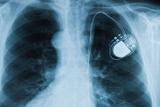

Около полумиллиона пациентов с установленными кардиостимуляторами находятся в группе риска в связи с возможной атакой хакеров. Фирма-производитель этого оборудования заявила о необходимости обновления...